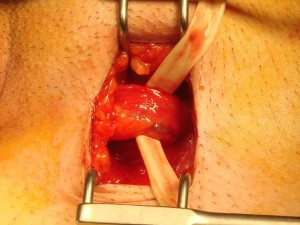

En la figura 2, se representan los diferentes pasos que realizamos en una varicocelectomía subinguinal.

Figura 2. Varicocelectomía subinguinal.

Inicialmente, realizamos un pequeña incisión en la piel (3–4 cm) a nivel inguinal, liberamos el cordón inguinal y con la ayuda de un vessel-loop levantamos el cordón inguinal. Posteriormente, abrimos las fascias espermáticas externa e interna y apreciamos las múltiples venas dilatadas que se entremezclan con la arteria testicular. Irrigamos ampliamente con papaverina para que la arteria se dilate y sea más fácil verla.